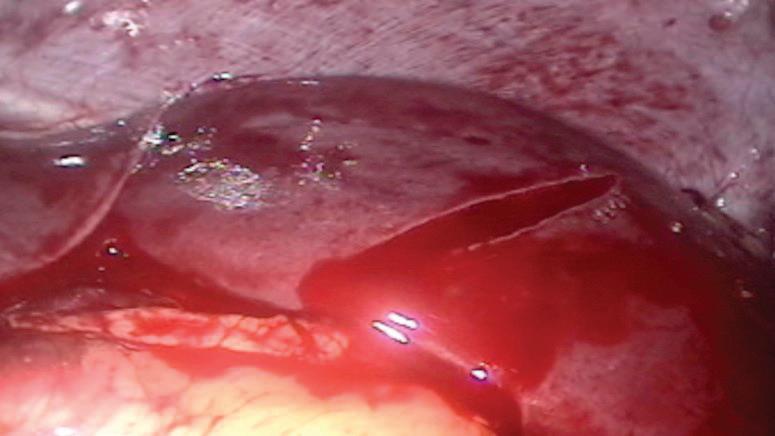

ЛЕЧЕНИЕ[11]

Хирургична тактика Нестабилните хемодинамично пациенти, заподозрени в нараняване на слезката и вътреабдоминални кръвоизливи, трябва да се подложат на диагностична лапаротомия с възстановяване или отстраняване на далака. Пациент с тъпа травма с данни за хемодинамична нестабилност, неотговаряща на ресусцитация с течности, без други признаци на външен кръвоизлив, трябва да се счита за наличие на животозастрашаващо увреждане на паренхимен орган (далак), докато не бъде доказано друго. Тези пациенти, които реагират на първоначален болус с течност, след което се влошават отново със спад на кръвното налягане и засилваща се тахикардия, също има вероятност да са получили животозастрашаващо увреждане на паренхимен орган с продължаващ кръвоизлив. Пациентите с компенсиран шок могат да бъдат лекувани чрез ангиоемболизация, но само ако може това да се извърши своевременно, еквивалентно на тази оперативна намеса. Основните определящи фактори при оперативната интервенция при стабилния пациент с увреждане на да

не или отстраняване на далака (Фиг.

Спешната лапаротомия на хемоперито -

неума

лис за лигиране. Медиалното въртене също прави по-лесно огледа на върха на далака и позволява възможно идентифициране на бифуркацията на далачната артерия. След като артерия и вена лиеналис се идентифицират и контролират чрез лигиране, късите стомашни съдове се идентифицират и лигират по подобен начин.